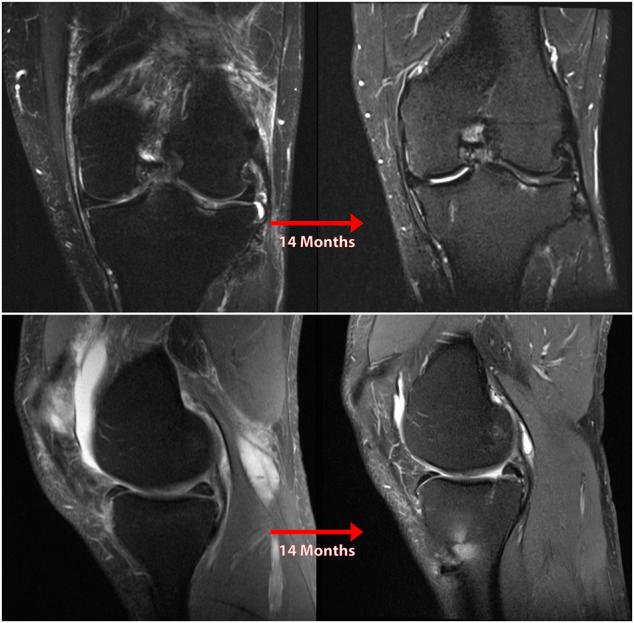

Posterior medial meniscus root tears (PMMRTs) make up a relatively notable proportion of all meniscus pathology and have been definitively linked to the progression of osteoarthritis (OA). While known risk factors for development of OA in the knee include abnormal tibial coronal alignment, obesity and female gender, PMMRTs have emerged in recent years as another significant driver of degenerative disease. These injuries lead to an increase in average contact pressure in the medial compartment, along with increases in peak contact pressure and a decrease in contact area relative to the intact state. Loss of the root attachment impairs the function of the entire meniscus and leads to meniscal extrusion, thus impairing the force-dissipating role of the meniscus. Anatomic meniscus root repairs with a transtibial pullout technique have been shown biomechanically to restore mean and peak contact pressures in the medial compartment. However, nonanatomic root repairs have been reported to be ineffective at restoring joint pressures back to normal. Meniscal extrusion is often a consequence of nonanatomic repair and is correlated with progression of OA. In this study, the authors will describe the biomechanical basis of the natural history of medial meniscal root tears and will support the biomechanical studies with a case series including patients that either underwent non-operative treatment (5 patients) or non-anatomic repair of their medial meniscal root tears (6 patients). Using measurements derived from axial MRI, the authors will detail the distance from native root attachment center of the non-anatomic tunnels and discuss the ongoing symptoms of those patients. Imaging and OA progression among patients who were treated nonoperatively before presentation to the authors will be discussed as well. The case series thus presented will illustrate the natural history of meniscal root tears, the consequences of non-anatomic repair, and the findings of symptomatic meniscal extrusion associated with a non-anatomic repair position of the meniscus.

后内侧半月板根部撕裂(PMMRTs)在所有半月板病变中占比较显著,并且已明确与骨关节炎(OA)的进展相关。虽然已知膝关节OA发展的风险因素包括胫骨冠状面排列异常、肥胖和女性性别,但近年来PMMRTs已成为退行性疾病的另一个重要驱动因素。这些损伤导致内侧间室平均接触压力增加,同时峰值接触压力增加,且相对于完整状态接触面积减小。根部附着的丧失会损害整个半月板的功能,并导致半月板挤出,从而损害半月板的力消散作用。经胫骨拉出技术进行的解剖学半月板根部修复在生物力学上已显示可恢复内侧间室的平均和峰值接触压力。然而,据报道非解剖学根部修复在将关节压力恢复到正常水平方面无效。半月板挤出通常是非解剖学修复的结果,并且与OA的进展相关。在本研究中,作者将描述内侧半月板根部撕裂自然病程的生物力学基础,并将通过一个病例系列来支持生物力学研究,该病例系列包括接受非手术治疗的患者(5例)或内侧半月板根部撕裂接受非解剖学修复的患者(6例)。作者将使用从轴向MRI得出的测量值,详细说明非解剖学隧道与天然根部附着中心的距离,并讨论这些患者的持续症状。还将讨论在向作者就诊之前接受非手术治疗的患者的影像学和OA进展情况。因此呈现的病例系列将说明半月板根部撕裂的自然病程、非解剖学修复的后果以及与半月板非解剖学修复位置相关的有症状半月板挤出的发现。